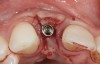

The following case report provides an example of this case scenario: A 24-year-old white male presented with congenitally missing tooth No. 26 restored with a single-tooth cement-retained implant restoration. The implant was placed excessively to the facial aspect of the edentulous site and too shallow, and the periodontal phenotype was thin scalloped (Figure 32). In an effort to mimic the lost midfacial soft tissues, pink ceramics were used as a cosmetic facade. Even though the restoration was not in the esthetic zone, the patient was highly displeased with the esthetic outcome and sought remediation.

The crown and screw-retained custom abutment were removed, and a surgical cover screw was placed into the implant, thereby allowing spontaneous gingival augmentation in situ (Figure 33 and Figure 34). Note that the lingual aspect of the implant site was significantly more coronal than the labial aspect, which was positive because the defect would be limited to a facial–lingual defect. A fixed RBR bridge was cemented on the adjacent teeth and used as a tooth-supported transitional provisional restoration (Figure 35). A few weeks were allotted to let the soft tissue heal and migrate around the cover screw (Figure 36) to see if there would be complete coverage, thereby allowing a soft-tissue augmentation procedure to be performed with primary flap closure as in clinical scenario No. 2. The major obstacle in achieving a positive tissue response was that the implant depth was also deficient because the implant–abutment connection was at the level of the free gingival margin. It was decided that the best treatment option would be to remove the implant. A high-powered reverse-torque device (Fixture Remover Kit, NeoBiotech, www.neobiotechus.com) was used to remove the implant atraumatically (Figure 38 through Figure 41). The implant socket was allowed to heal for several months not unlike an extracted tooth (Figure 42). A new implant was placed in a better position from both a restorative and esthetic perspective (Figure 43), and after a few months of healing, a new crown was made (Figure 44). A satisfactory functional and esthetic result was achieved (Figure 45 and Figure 46) without employing pink porcelain.

Fig 32. A dissatisfied patient presented with significant midfacial recession of implant restoration of tooth No. 26. Pink ceramic material was used unsuccessfully to prosthodontically compensate for the lost midfacial tissue.

Fig 33. Excessive facial angulation of the implant placement shown with an abutment driver in the access screw hole.

Fig 34. A surgical cover screw was placed in an attempt to decoronate the implant and gain soft-tissue coverage in situ.